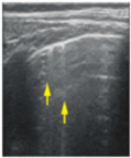

- Sparse B-lines (Figure 3a)—100%;

Figure 3. The lung ultrasound showed (a) sparse B-lines with small zones of pleural irregularities corresponding to a LUSS = 1; (b) confluent B-lines with aspect of ‘white-lung ‘corresponding to LUSS = 2. - Confluent or coalescent B-lines (Figure 3b)—57.89%;